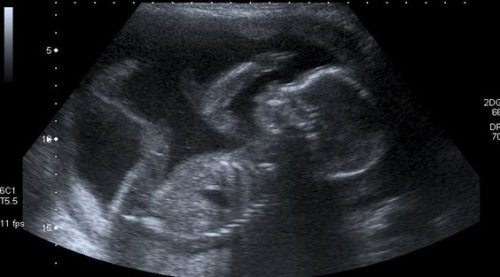

En kvinne vet at hun er en mor på sin første ultralyd. Hun kan ikke holde tårene tilbake når hun hører barnets raske hjerteslag. Hennes eget hjerte slår like raskt. Hun blir overveldet av glede over denne første kontakten med sitt ufødte barn.

Den engstelige moren drømmer om den dagen hun får holde sin lille solstråle i armene for første gang. Hun vet at de er knyttet sammen for resten av livet. Hver ultralyd, hver lille bevegelse, blir en milepæl i morens liv.

Imidlertid vet moren godt at hun har må vente en god stund. De neste ni månedene må hun nøye seg med uklare ultralydbilder på en svart-hvittskjerm. Dette før hun kan møte sin sønn eller datter ansikt til ansikt og se fargen på barnets hud, hår og øyne.